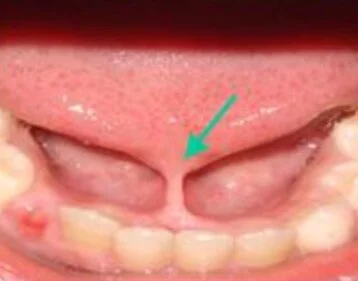

Posterior Tongue Tie

Posterior tongue-ties are commonly over-looked because they’re usually not obvious at first glance. The restriction is more towards the back of the tongue. Visual signs of a posterior tongue-tie are subtle but symptoms of tongue restriction and dysfunction are very similar to an anterior tongue-tie.

Photo from CEFAC